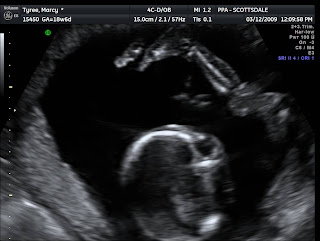

Wes and I are excited to announce that we are expecting another baby.  We found out a few weeks ago that it is a boy.  We are thrilled that Alex is going to have a little brother to play with.  I am almost half way through this pregnancy. It is going by so fast!!  This past week we had our Level 2 ultrasound. DJ (Wes' nickname for the baby) looks great.  I was really excited to have my mom at the ultrasound appointment with me.  Here are some pictures from the ultrasound. We are looking forward to DJ's arrival in early August.

DJ's profile.....isn't he cute!!!